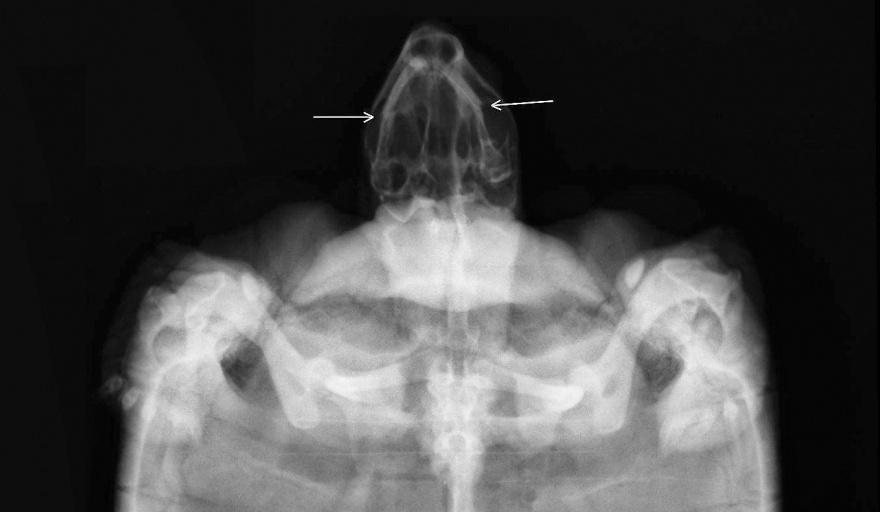

En las mismas se observa fractura del tercio medio de ambas caras mandibulares con leve desplazamiento de cabos hacia lateral.

Se realiza radiografía de control a los 6 meses del traumatismo donde se evidencia cicatrización ósea en proceso.